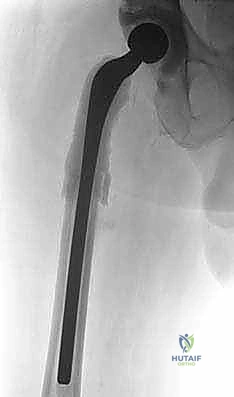

ماستر كلاس: جراحة استبدال مفصل الورك على مرحلتين لعلاج التهاب المفصل المزمن بعد الجراحة باستخدام فاصل محمل بالمضادات الحيوية

المرحلة الثانية: إعادة البناء وتركيب المفصل النهائي (Re-implantation)

بعد التأكد التام من القضاء على العدوى (سريرياً ومخبرياً)، وتوقف المريض عن تناول المضادات الحيوية لمدة أسبوعين على